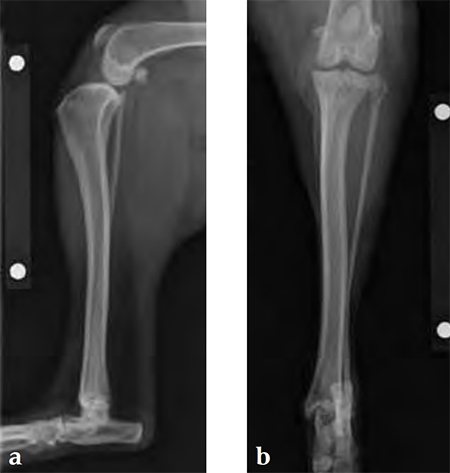

An 8-year-old, female, spayed, 24 kg Australian cattle dog. This breed has short stocky legs and is very energetic and strong. The added strength of the 3.5 mm plate over the TPLO 2.7 mm plate was an advantage. The smaller head profile and shorter length of the TPLO 3.5 mm small stature plate allowed it to fit nicely on this patient.